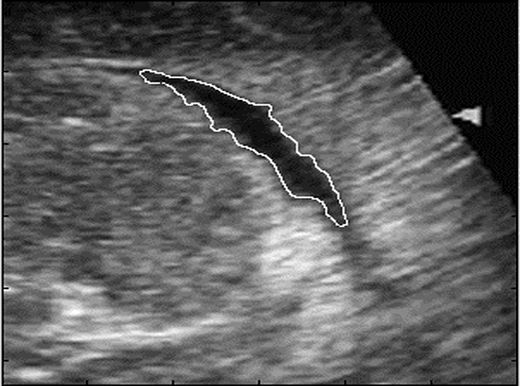

• Level Sets Detection Algorithm for Ultrasound Images

This paper describes a technique based on the Osher and Shethian level-sets approach of recovering object's shape in ultrasound medical images.